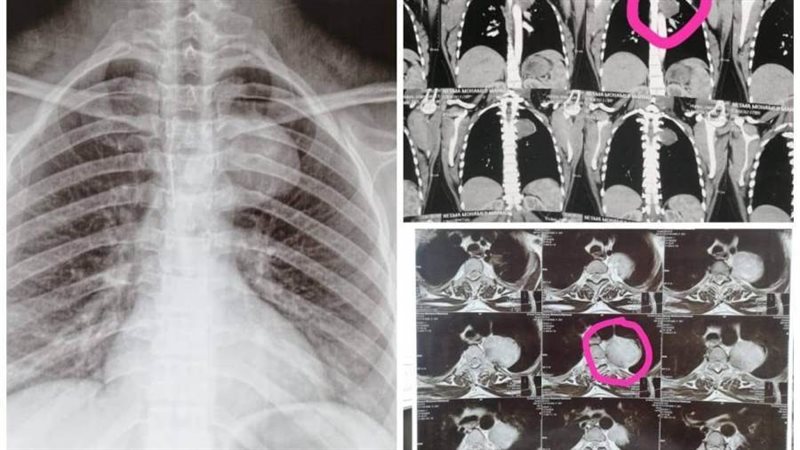

كان مستشفى الأمراض العصبية والنفسية وجراحة المخ والأعصاب برئاسة الأستاذ الدكتور طارق راجح، وقد استقبل سيدة تبلغ من العمر ٢٥ عاما، حامل في شهرها الأول، وتعاني من التهابات رئوية متكررة، وبعد فحصها من قبل فريق من المتخصصين بقسم الأمراض الصدرية، تحت إشراف الأستاذة الدكتورة صفاء وافي، والأطباء صفاء عبد الجيد، استشاري الأمراض الصدرية، والطبيب يوسف ثروت، طبيب مقيم بالقسم، بمشاركة الطبيبة شروق كيلاني، مدرس مساعد بقسم طب القلب، أظهرت الأشعات وجود ورم معقد بالعمود الفقري ممتد إلى الرئة.

ونظراً لخطورة الحالة، تم على الفور تشكيل لجنة علمية ضمت نخبة من الاستشاريين، وأقرت اللجنة بالإجماع ضرورة إجراء عملية جراحية عاجلة لاستئصال الورم.